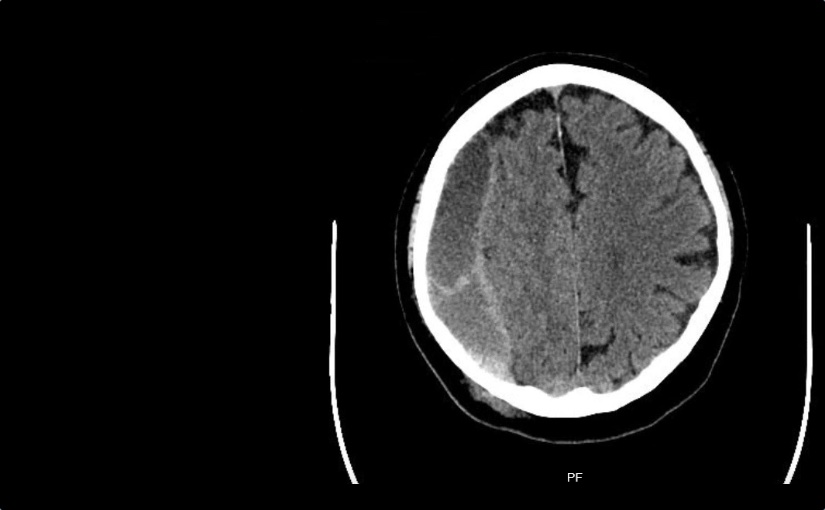

Vorwort Ja, wir sind keine Radiologen. Ja, in der heutigen Zeit, in der es immer mehr um medikolegale Konsequenzen unseres Tuns geht, sollten wir uns nicht überschätzen und selbst radiologische Befunde erheben ohne die formale Qualifikation dafür zu haben. Ja, auch fachärztliche radiologische Befunde sind oft falsch (oder mindestens diskutabel). Ja, ich erwarte von allen…